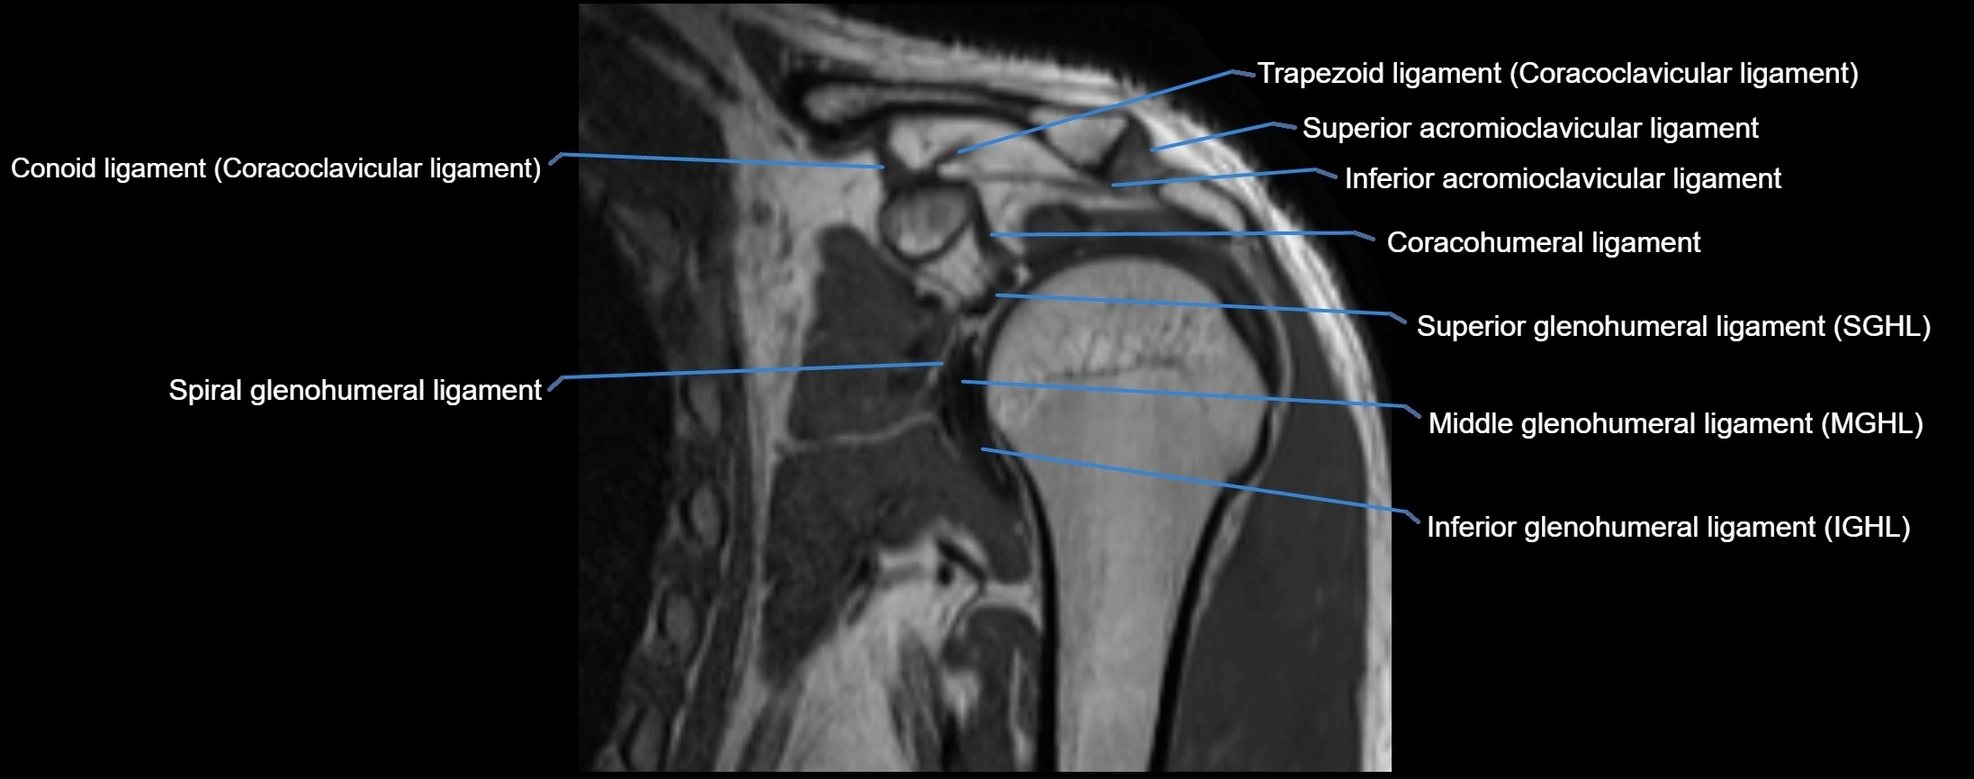

MRI Appearance

• T1-weighted images:

• Normal ligament: Low signal (dark linear band) spanning acromion to clavicle.

• Surrounding fat planes: Bright, delineating the ligament clearly.

• Marrow of clavicle and acromion: Bright due to fatty content.

• Tears: Discontinuity or irregular thickening with intermediate-to-bright signal.

• Chronic injury: Thinning, fraying, or irregular low-signal fibers with adjacent scarring.

• T2-weighted images:

• Normal ligament: Low signal, homogeneous.

• Partial tear or sprain: Focal hyperintensity or thickening.

• Complete tear: Discontinuity with fluid-bright gap between clavicle and acromion.

• Associated edema: Bright signal in distal clavicle or acromion marrow.

• STIR:

• Normal ligament: Dark linear band.

• Injury or inflammation: Bright hyperintense signal in and around ligament fibers.

• Highlights periligamentous soft-tissue edema, especially in acute trauma.

• Proton Density Fat-Saturated (PD FS):

• Normal ligament: Low signal, uniform thickness.

• Partial tear or sprain: Bright signal or contour irregularity.

• Complete tear: Clear discontinuity with bright signal gap and joint effusion.

• Excellent for assessing joint capsule, coracoclavicular ligaments, and periarticular edema.

MRI images

image